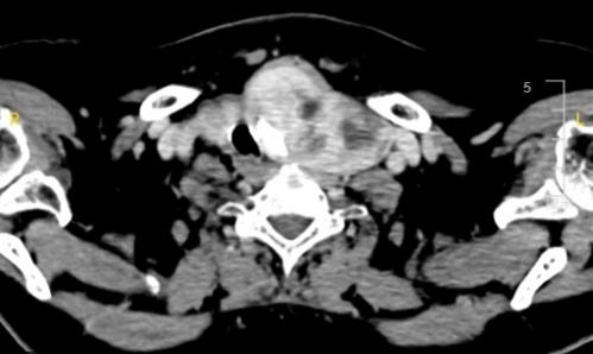

患者考虑甲状腺肿物压迫气道合并肺部感染、ARDS可能,于2022年9月1日行左侧胸骨后巨大甲状腺肿块切除 + 左侧喉返神经探查 + 术中快速病检术。术中探查:右侧甲状腺I度肿大,手指扪诊可扪及多个大小不一肿块,质硬,包膜完整,分界清楚。左侧甲状腺III度弥漫性肿大,伸入胸骨后,约13.0 × 15.0 × 10.0 cm肿块,质地硬,气管明显受压右偏狭窄。术中快速病检回报:左侧甲状腺组织内大量淋巴样细胞较弥漫分布,细胞较一致,考虑为淋巴组织增生性病变。术后常规病理及免疫组化诊断为:左侧甲状腺组织正常结构消失,其内见大量淋巴样细胞增生及浸润性生长,并浸润至周围脂肪及横纹肌组织,符合高侵袭性非霍奇金B细胞性淋巴瘤,考虑弥漫大B细胞淋巴瘤,生发中心来源。CK-pan (−),CD20 (+),CD79α (+),CD3 (+),CD5 (+),CD21 (FDC网增生伴破坏),Bcl-2 (−),Ki-67 (约80%+),CD10 (−),EBER (−),Bcl-6 (+),Mum-1 (−),CyclinD1 (−),C-myc(−),P53 (野生型表达) (见图2(a)~(d))。术后转入ICU治疗,期间予地塞米松10 mg静滴、每日1次,后因患者呼酸合并代谢性碱中毒代偿期、气道严重狭窄、I型呼衰,于2022年9月9日全麻下行气管切开术,并拒绝化疗。2022年9月13日转回甲状腺、胃肠、疝外科继续治疗,2022年9月19日因呼吸困难、氧合差再入ICU,纤支镜检查见气切以气道狭窄套管内粘稠痰痂,经冲洗后继续机械通气,氧合改善,后于2022年9月22日出院,后续未于本院继续治疗,因病情进一步进展,通过随访发现患者于出院20 d后死亡。

(a) (b) (c) (d)

(a) 甲状腺组织内大量淋巴细胞增生及浸润性生长;(b) 肿瘤细胞CD20 (+);(c) 肿瘤细胞CD79a (+);(d) Ki-67 (约80%+)。

Figure 2. Pathological examination findings of left thyroid mass (20×)

2. 左侧甲状腺包块病理检查结果(20×)